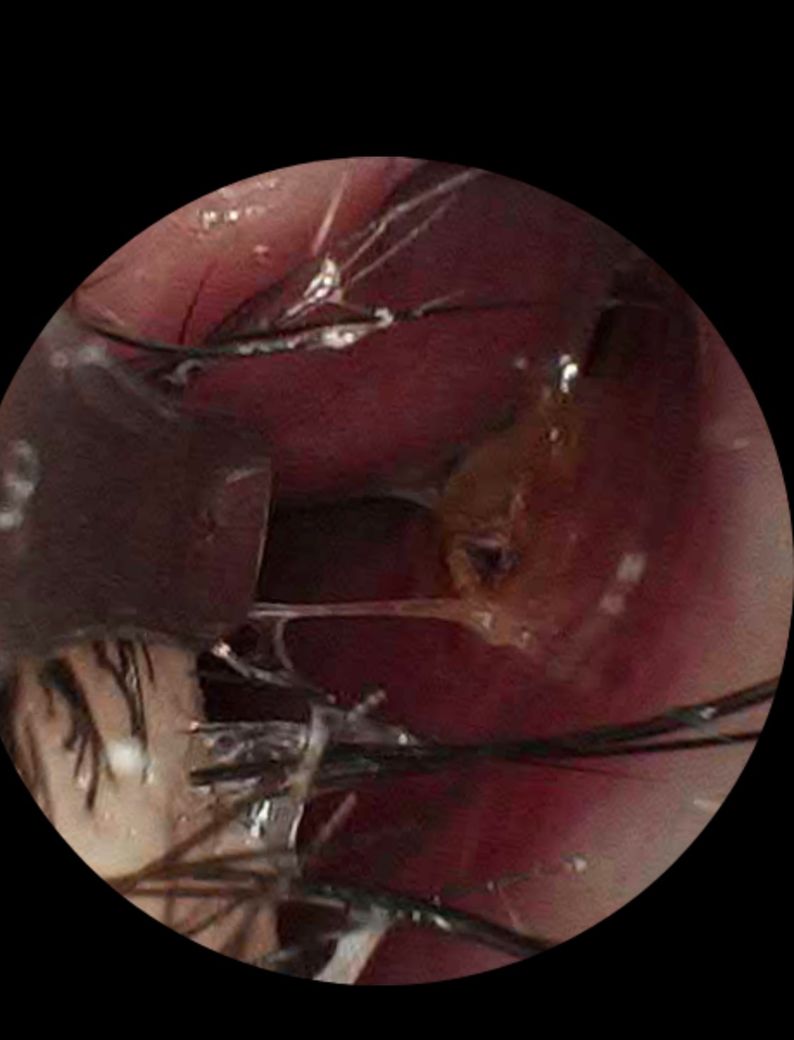

콧속 점막에 딱지처럼 분비물이 단단히 붙어 있고 이물감이 지속됩니다. 콧물은 밖으로 잘 나오지 않지만 뒤로 넘어가는 느낌(후비루)이 있으며,실제로도 목쪽으로 소량 넘어 갑니다. 간헐적인 코막힘과 약간의 건조감, 가끔 찌르는 듯하거나 시린 느낌도 있습니다. 이러한 증상은 1년 이상 지속되었습니다.

이런 경우 알레르기 외 비알레르기/건조성 비염 가능성이 있는지, 점막에 붙어 있는 딱지가 염증 소견인지 궁금합니다. 또한 현재 상태에서 항생제 복용이 필요한지, 추가 또는 연장이 필요한 상황인지에 대해 조언 부탁드립니다.

• 1번 째 사진

설명하신 양상은 알레르기 비염보다는 비알레르기성, 특히 건조성 또는 만성 자극성 비염 가능성이 높습니다. 알레르기 검사 정상, 딱지처럼 붙은 분비물, 후비루, 건조감과 시린 느낌이 장기간 지속된 점이 이에 부합합니다.

콧속 딱지는 대개 점막 건조와 분비물 농축으로 생기며, 고름·악취·발열이 없다면 활동성 세균 감염 소견은 아닙니다. 현재 증상만으로는 항생제 추가나 연장은 필요해 보이지 않습니다.

치료는 생리식염수 세척, 가습, 비강 자극 회피가 기본이며 필요 시 국소 스테로이드나 보습 목적 치료를 고려합니다. 정확한 판단은 비내시경으로 딱지 제거 후 점막 상태 확인이 도움이 됩니다.